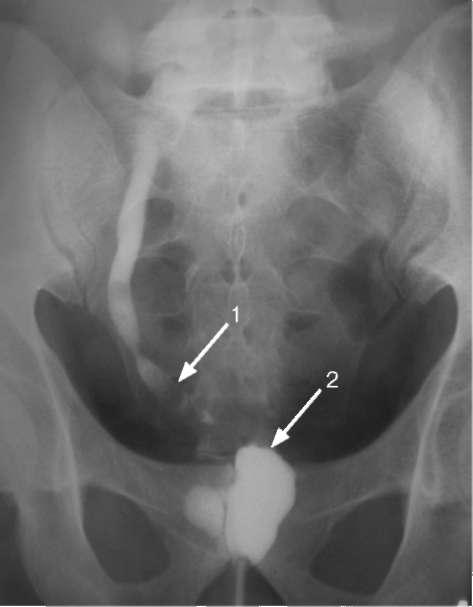

Медицинские изображения и примеры эксреторной цистографии